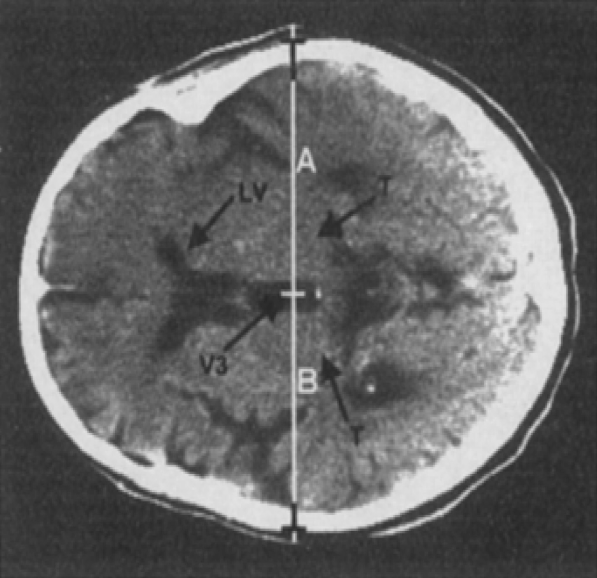

超声结构性评估定性监测 ICP 主要通过中线结构是否存在位移判断。可在图像中间观察到蝴蝶形的低回声的中脑脑干成像。将探头角度向间脑和脑室倾斜可以显示三脑室和侧脑室正面,可见到明显的超声波遇到室管膜正交平面形成的高回声线边界( 又称双轨征 ),即正常的颅脑中线位置[24]。根据双轨征到两侧颅骨的距离是否相等判断颅脑中线移位情况 ( 图 1-1)。